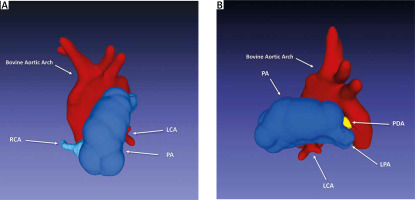

At the age of 5 months, he was admitted to our center for a PDA assessment. On physical examination, a continuous murmur was found. A chest X-ray revealed cardiomegaly. The electrocardiogram showed a normal sinus rhythm with signs of left ventricular hypertrophy. TTE established the diagnosis of PDA (4 mm) with left-to-right shunt, small PFO, and mild left ventricular dilation with preserved systolic function. The patient had cardiac catheterization for PDA assessment, which revealed an unexpected finding: an apparent ARCAPA originating from the pulmonary artery and a PDA measuring 4 × 4 mm (Figures 1 A, B). Moreover, computed tomography confirmed and showed the right coronary artery (RCA) arising from the right anterior sinus of pulmonary artery, bovine aortic arch, and a PDA of 3.5 mm in diameter and 2 mm in length (Figures 2 A, B).

Figure 2

3D reconstruction model. A – Anterior view showing the anomalous origin of the right coronary artery from the pulmonary artery (ARCAPA), and the bovine aortic arch can also be seen. B – Lateral view showing the patent ductus arteriosus (PDA) (yellow) and normal origin of left main coronary artery (LCA)

LPA – left pulmonary artery, PA – pulmonary artery, RCA – right coronary artery.